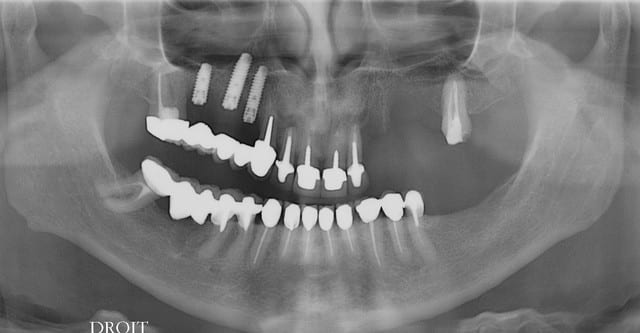

Positionnement implantaire surprenant !

le type à une forme d'arcade très rectangulaire ?

c'est parce qu'il expanse.